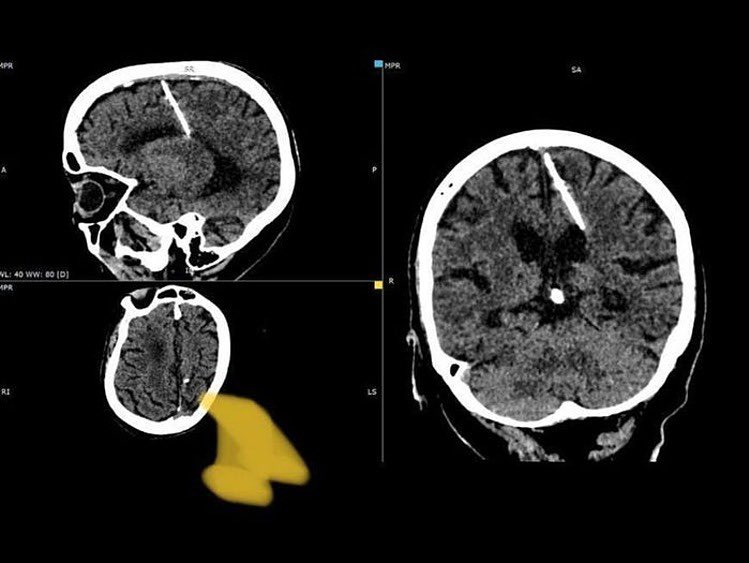

रुसमा एउटा अचम्मको घटना बाहिर आएको छ । त्यहाँ ८० वर्षीया महिलाको मस्तिष्कमा ३ सेन्टिमिटर लामो सुई भेटिएको छ । ती महिलाले आफ्नो सम्पूर्ण जीवन यही सुईको साथ बिताइन्। डाक्टरहरूले सिटि स्क्यान गर्दा यो कुरा थाहा पाएका छन् । बैज्ञानिकहरुले यो घटनालाई भ्रुण हत्याको प्रयास भएको मानेका छन् चिकित्सक भन्छन् कि ती महिलाका आमाबाबुले मार्न चाहेको हुन सक्छ, तर तिनीहरू असफल भए ।

विज्ञप्तिमा भनिएको छ कि यस्ता विधिहरू प्रायः अपराधको प्रमाण लुकाउन प्रयोग गरिन्छ। युद्धको समयमा सोभियत संघमा खाद्यान्न अभाव थियो। जनता गरिबीमा बाँचिरहेका थिए । महिलाको देब्रे भागमा सुई पसेको स्थानीय विभागले जनाएको छ । तर त्यसको कुनै असर भएन र बालिका बाँचिन् ।